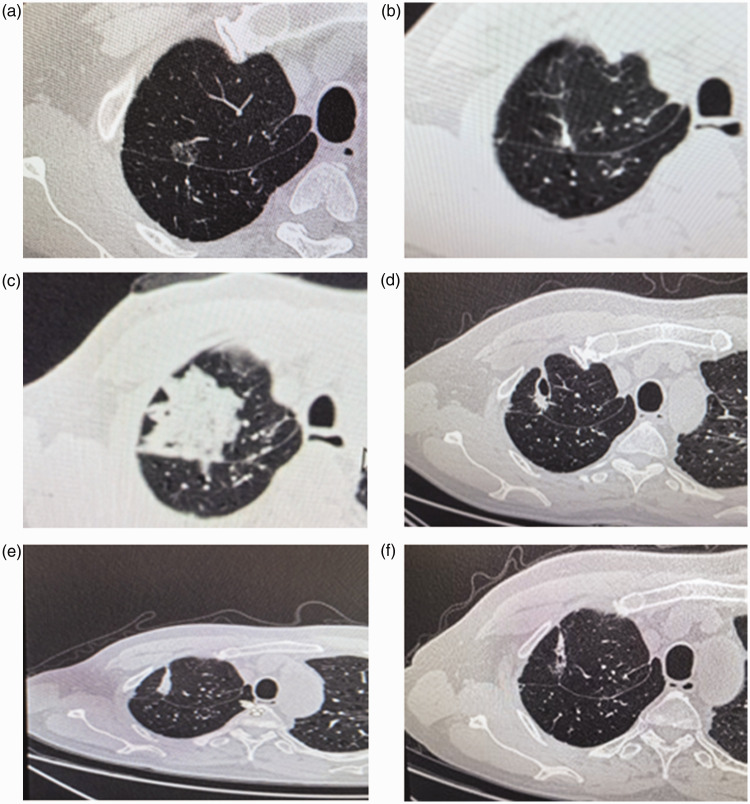

肺癌仍然是全球癌症相关死亡的主要原因。术后复发的患者通常有有限的治疗选择。本研究评估了计算机断层扫描引导下射频消融治疗肺癌手术后不适合再手术的高危肺结节的安全性和可行性。方法回顾性分析2023年7月~ 2024年8月在华西医院行射频消融治疗的肺癌术后放射学可疑复发结节患者40例(男16例,女24例,年龄41 ~ 78岁)。结果包括手术成功、并发症发生、住院时间、30天死亡率和影像学反应。结果所有手术在技术上均成功。12.5%的患者出现5个轻微并发症,包括发热(n = 2)和气胸(n = 3)。30天内未发生死亡,未观察到重大不良事件(如血胸)。术后平均住院时间为2.0天。此外,82.5%的患者接受了随访,并在3个月时实现了完全消融。结论ct引导下射频消融是一种微创、安全、有效的治疗肺癌术后不适合再手术的高危肺结节的方法。其低并发症率、快速恢复和有希望的局部控制支持其集成到多模式治疗算法中。需要更大规模的前瞻性研究来验证长期结果。

BackgroundLung cancer remains the leading cause of cancer-related deaths globally. Patients with postoperative recurrence typically have limited treatment options. This study evaluated the safety and feasibility of computed tomography-guided radiofrequency ablation for treating high-risk pulmonary nodules in patients who have undergone lung cancer surgery and are ineligible for reoperation.MethodsWe retrospectively analyzed 40 patients (16 men and 24 women, aged 41-78 years) with radiologically suspicious recurrent nodules following lung cancer resection who were treated with radiofrequency ablation at West China Hospital (July 2023-August 2024). Outcomes included procedural success, occurrence of complications, hospitalization duration, 30-day mortality, and imaging response.ResultsAll procedures were technically successful. Five minor complications occurred in 12.5% of the patients, including fever (n = 2) and pneumothorax (n = 3). No deaths occurred within 30 days, and no major adverse events (e.g. hemothorax) were observed. The median postoperative length of hospital stay after ablation was 2.0 days. Furthermore, 82.5% of the patients were followed up and had achieved complete ablation at the 3-month mark.ConclusionComputed tomography-guided radiofrequency ablation is a minimally invasive, safe, and effective option for managing high-risk pulmonary nodules in postoperative lung cancer patients who are deemed ineligible for reoperation. Its low complication rate, rapid recovery, and promising local control support its integration into multimodal treatment algorithms. Larger prospective studies are needed to validate long-term outcomes.